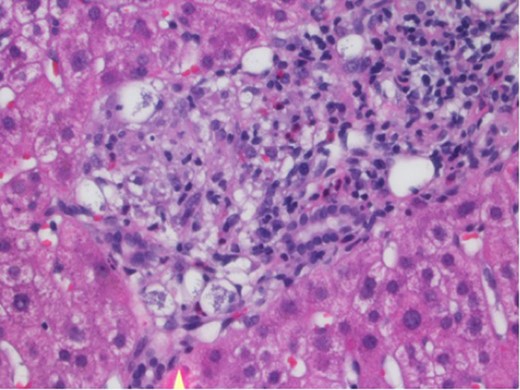

In March 2017, the patient presented with 2 weeks of generalized body aches, fevers, mild congestion and dysuria. His transaminases worsened—AST 360 U/L, ALT 387 U/L. Blood, urine and sputum cultures grew no organisms and the patient had a normal chest radiograph and abdominal ultrasound. CT sinus, obtained to rule out sinusitis, remarked on few mucous retention cysts of the maxillary sinuses, but was otherwise negative for any other pathology. However, further interrogation found that the patient had significant opportunistic infection exposure risk; the patient was a butcher at a local grocery store, and owned a new rabbit, several parakeets and four dogs. A repeat liver biopsy was performed, and this time, was found to have predominantly lobular, and occasionally portal, epithelioid granulomas (Fig. 1) with intracellular yeast-like elements (Fig. 2). These were described as narrow-based budding yeasts favoring histoplasma (Fig. 3). No portal based features of acute rejection were noted and bile ducts were preserved in the majority of portal tracts. Urine histoplasma antigen testing corroborated the histology finding—the patient had progressive disseminated histoplasmosis manifested as granulomatous hepatitis. He completed an 11-day course of liposomal amphotericin B and will continue itraconazole therapy for a year. His immunosuppression regimen was significantly decreased and mycophenolate was stopped. The most recent liver biopsy in May 2017 revealed a persistent—though significantly decreased—lobular inflammation, microgranulomas and budding yeast elements. His transaminases remain elevated at AST 265 U/L and ALT 259 U/L. He will continue close follow up to ensure further improvement on current therapy and resolution of Histoplasmosis.

Portal granuloma with histiocytes containing multiple intracytoplasmic yeast-like fungi. Hematoxylin and Eosin stain ×400.